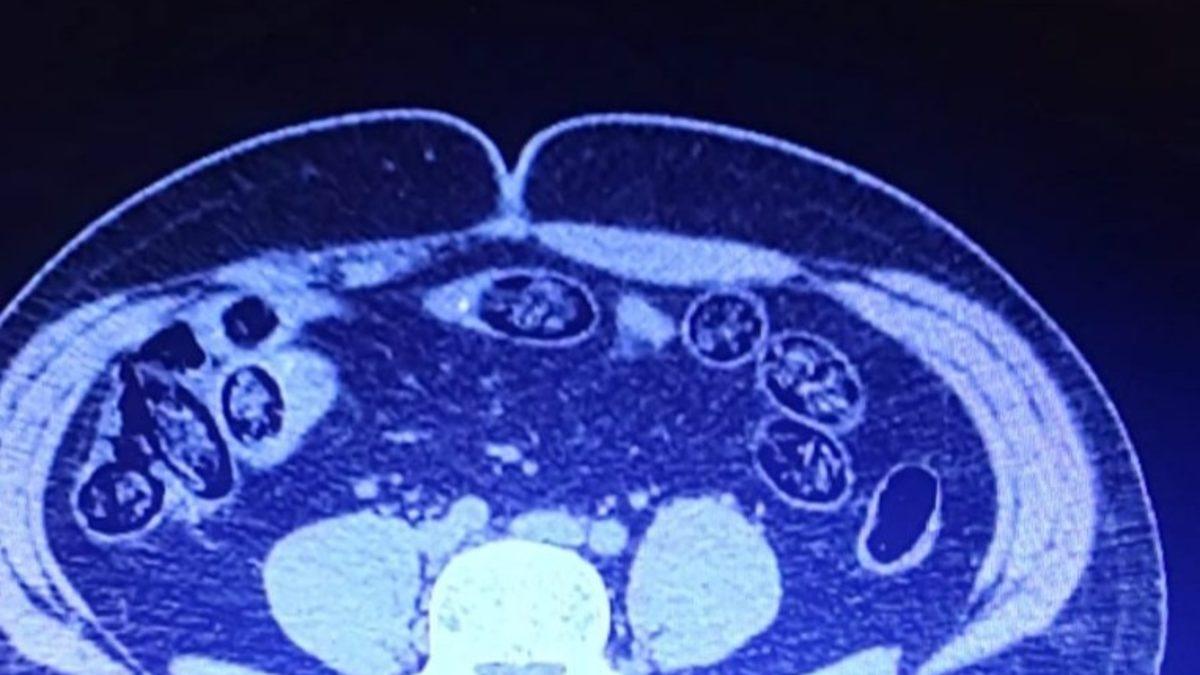

Van’dan uçakla İzmir’e gitmek isterken havalimanında yakalanan 2 İranlının yapılan muayenesinde toplamda 103 adet kapsül halinde 920 gram metanfetamin maddesi ele geçirildi.Van Emniyet Müdürlüğünden yapılan açıklamada, Narkotik Suçlarla Mücadele Şube Müdürlüğü görevlilerince yapılan risk analizi çalışmaları neticesinde İran uyruklu A.D.